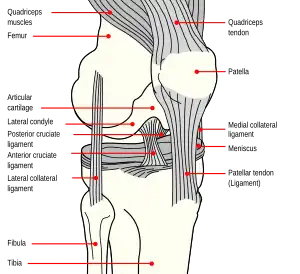

Anatomy of the knee

The patella is a triangular sesamoid bone that is embedded in tendon. It rests in the patellofemoral groove, an articular cartilage-lined hollow at the end of the thigh bone (femur) where the thigh bone meets the shin bone (tibia). Several ligaments and tendons hold the patella in place and allow it to move up and down the patellofemoral groove when the leg bends. The top of the patella attaches to the quadriceps muscle via the quadriceps tendon,[2] the middle to the vastus medialis obliquus and vastus lateralis muscles, and the bottom to the head of the tibia (tibial tuberosity) via the patellar tendon, which is a continuation of the quadriceps femoris tendon.[13] The medial patellofemoral ligament attaches horizontally in the inner knee to the adductor magnus tendon and is the structure most often damaged during a patellar dislocation. Finally, the lateral collateral ligament and the medial collateral ligament stabilize the patella on either side.[2] Any of these structures can sustain damage during a patellar dislocation.